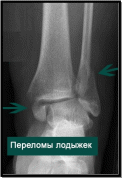

19. Переломы костей голени в детском возрасте. Переломы дистального отдела костей голени – переломы лодыжек, метафизарные переломы. Клиника, диагностика, принципы лечения.

Повреждения области дистального отдела костей голени характерны для детского возраста, в отличие от повреждений проксимального конца. Травма происходит в момент скручивания при фиксированной стопе, при этом вид перелома зависит от положения стопы в момент травмы. Также возможен перелом при прямой травме, путем сдавления (падение тяжелого предмета), падении с высоты и приземлении на согнутые ноги. При этом внимательно следует отнестись к костям стопы, так как возможно их сочетанное повреждение при данном механизме травмы.

Переломы лодыжек наблюдаются преимущественно у детей старшего школьного возраста и редко сопровождаются смещением отломков. Чаще возникает перелом внутренней лодыжки по краю эпифиза или отрыв в средней ее трети

Клиническая картина при неполных переломах весьма скудная. Ребенок жалуется на умеренную боль при движениях в голеностопном суставе. Имеется припухлость в зоне повреждения и болезненность при пальпации.

Перелом со смещением отломков сопровождается значительным отеком и деформацией области голеностопного сустава. Ребенок не может наступать на ногу, движения в суставе резко ограничены из-за болезненности.

Для первичной диагностики выполняется рентгенография. При повреждении внутрисуставных структур для определения тактики дальнейшего лечения дополнительно выполняется КТ.

Лечение переломов лодыжек без смещения отломков проводят в амбулаторных условиях. Иммобилизацию осуществляют гипсовым лонгетом, который накладывают до коленного сустава сроком на 2—3 недели.